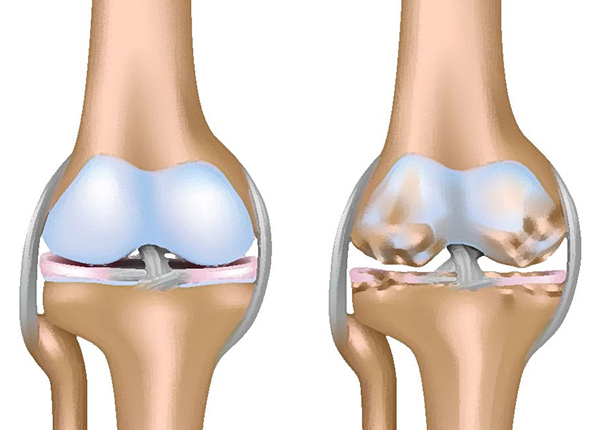

Người bệnh bị u xương có nguy hiểm không?

U xương là một bệnh lý liên quan đến sự phát triển bất thường của...